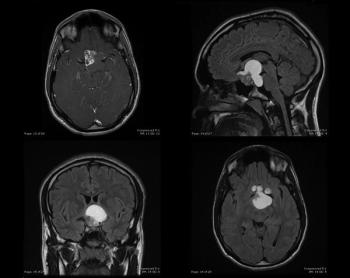

Young Man With a History of Headaches and Blurred VisionPublished: March 21st 2013 | Updated: